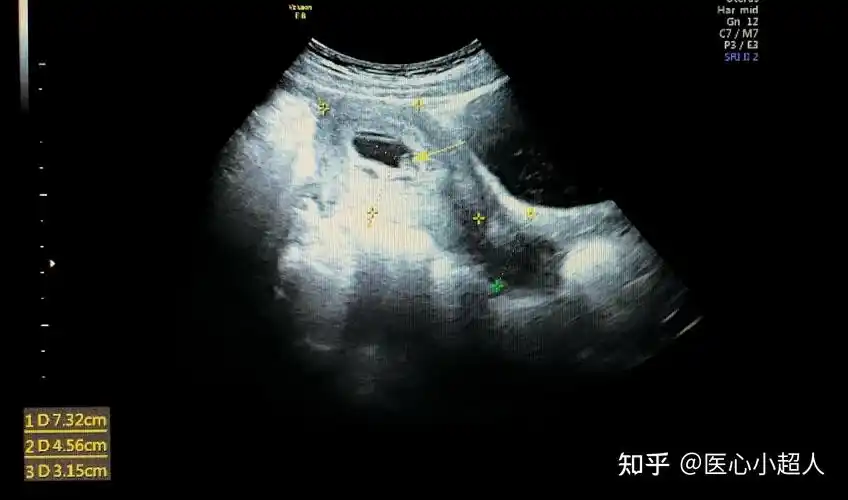

正常早期妊娠子宫超声所见(一)